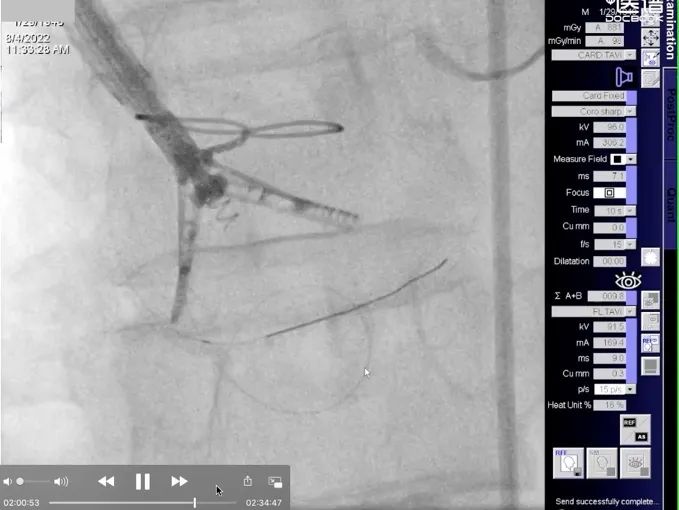

手术过程

患者全麻后,右侧颈静脉穿刺,将K-Clip®输送系统送达右心房内。在超声医生指引下,对K-Clip®的输送系统进行调姿,将K-Clip®锚定到位。

到位后,将K-Clip®夹持臂打开到最大,对目标瓣环位置进行夹合。判定三尖瓣反流减少程度满意后,解离夹合件,退出输送系统。

术后评估三尖瓣反流程度从重度反流(4+)下降为轻中度(1~2+)反流,评估冠脉血流通畅,令人满意,即结束手术。手术在1小时内完成,器械操作时间30分钟。